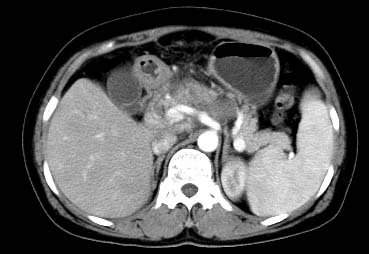

以下是引用西北一只狼在2008-6-30 20:58:00的发言:[br]肝左叶胆管细胞ca并肝门淋巴结转移、胰腺、胃小弯浸润

以下是引用ydx_74在2008-6-30 21:54:00的发言:[br]左叶胆管细胞ca并肝门淋巴结转移、胰腺、胃小弯浸润